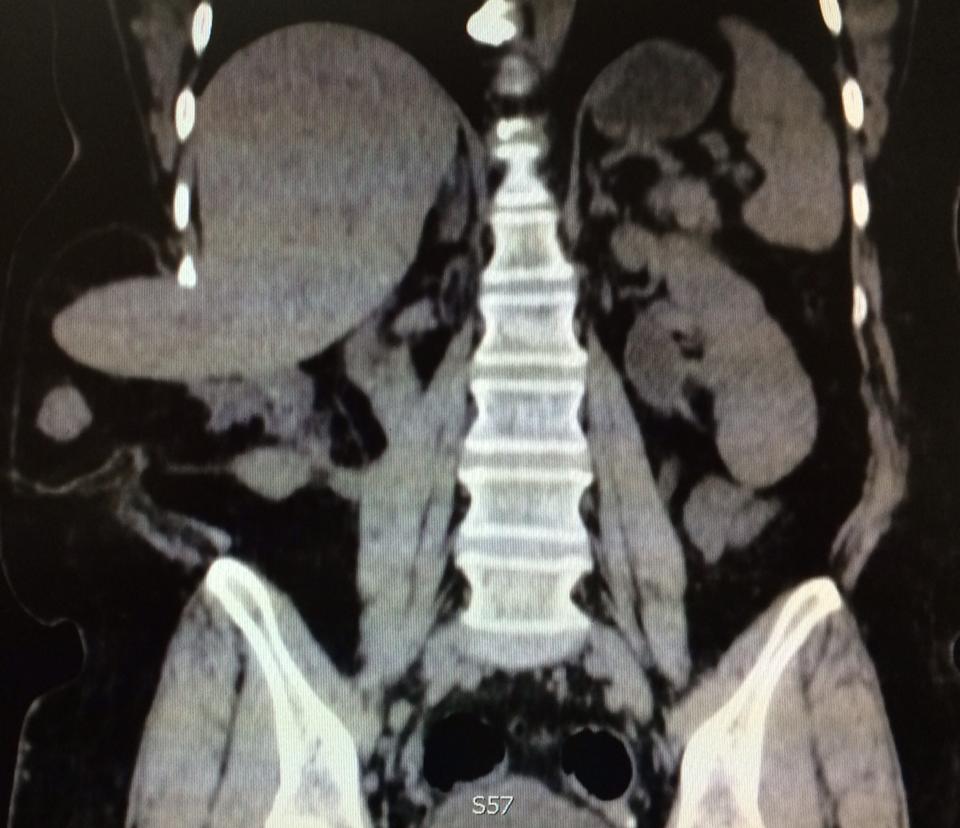

Complicated SSTIs can also be labeled as non-necrotizing or necrotizing infections. Necrotizing infections maximum typically contain the muscular fascial layers but may additionally contain the dermal, subcutaneous, and muscle layers and warrant activated, competitive surgical debridement.

Necrotizing SSTIs (cellulitis, fasciitis, myositis, Fournier’s gangrene) require surgical intervention which includes drainage and debridement of necrotic tissue further to antibiotic remedy.